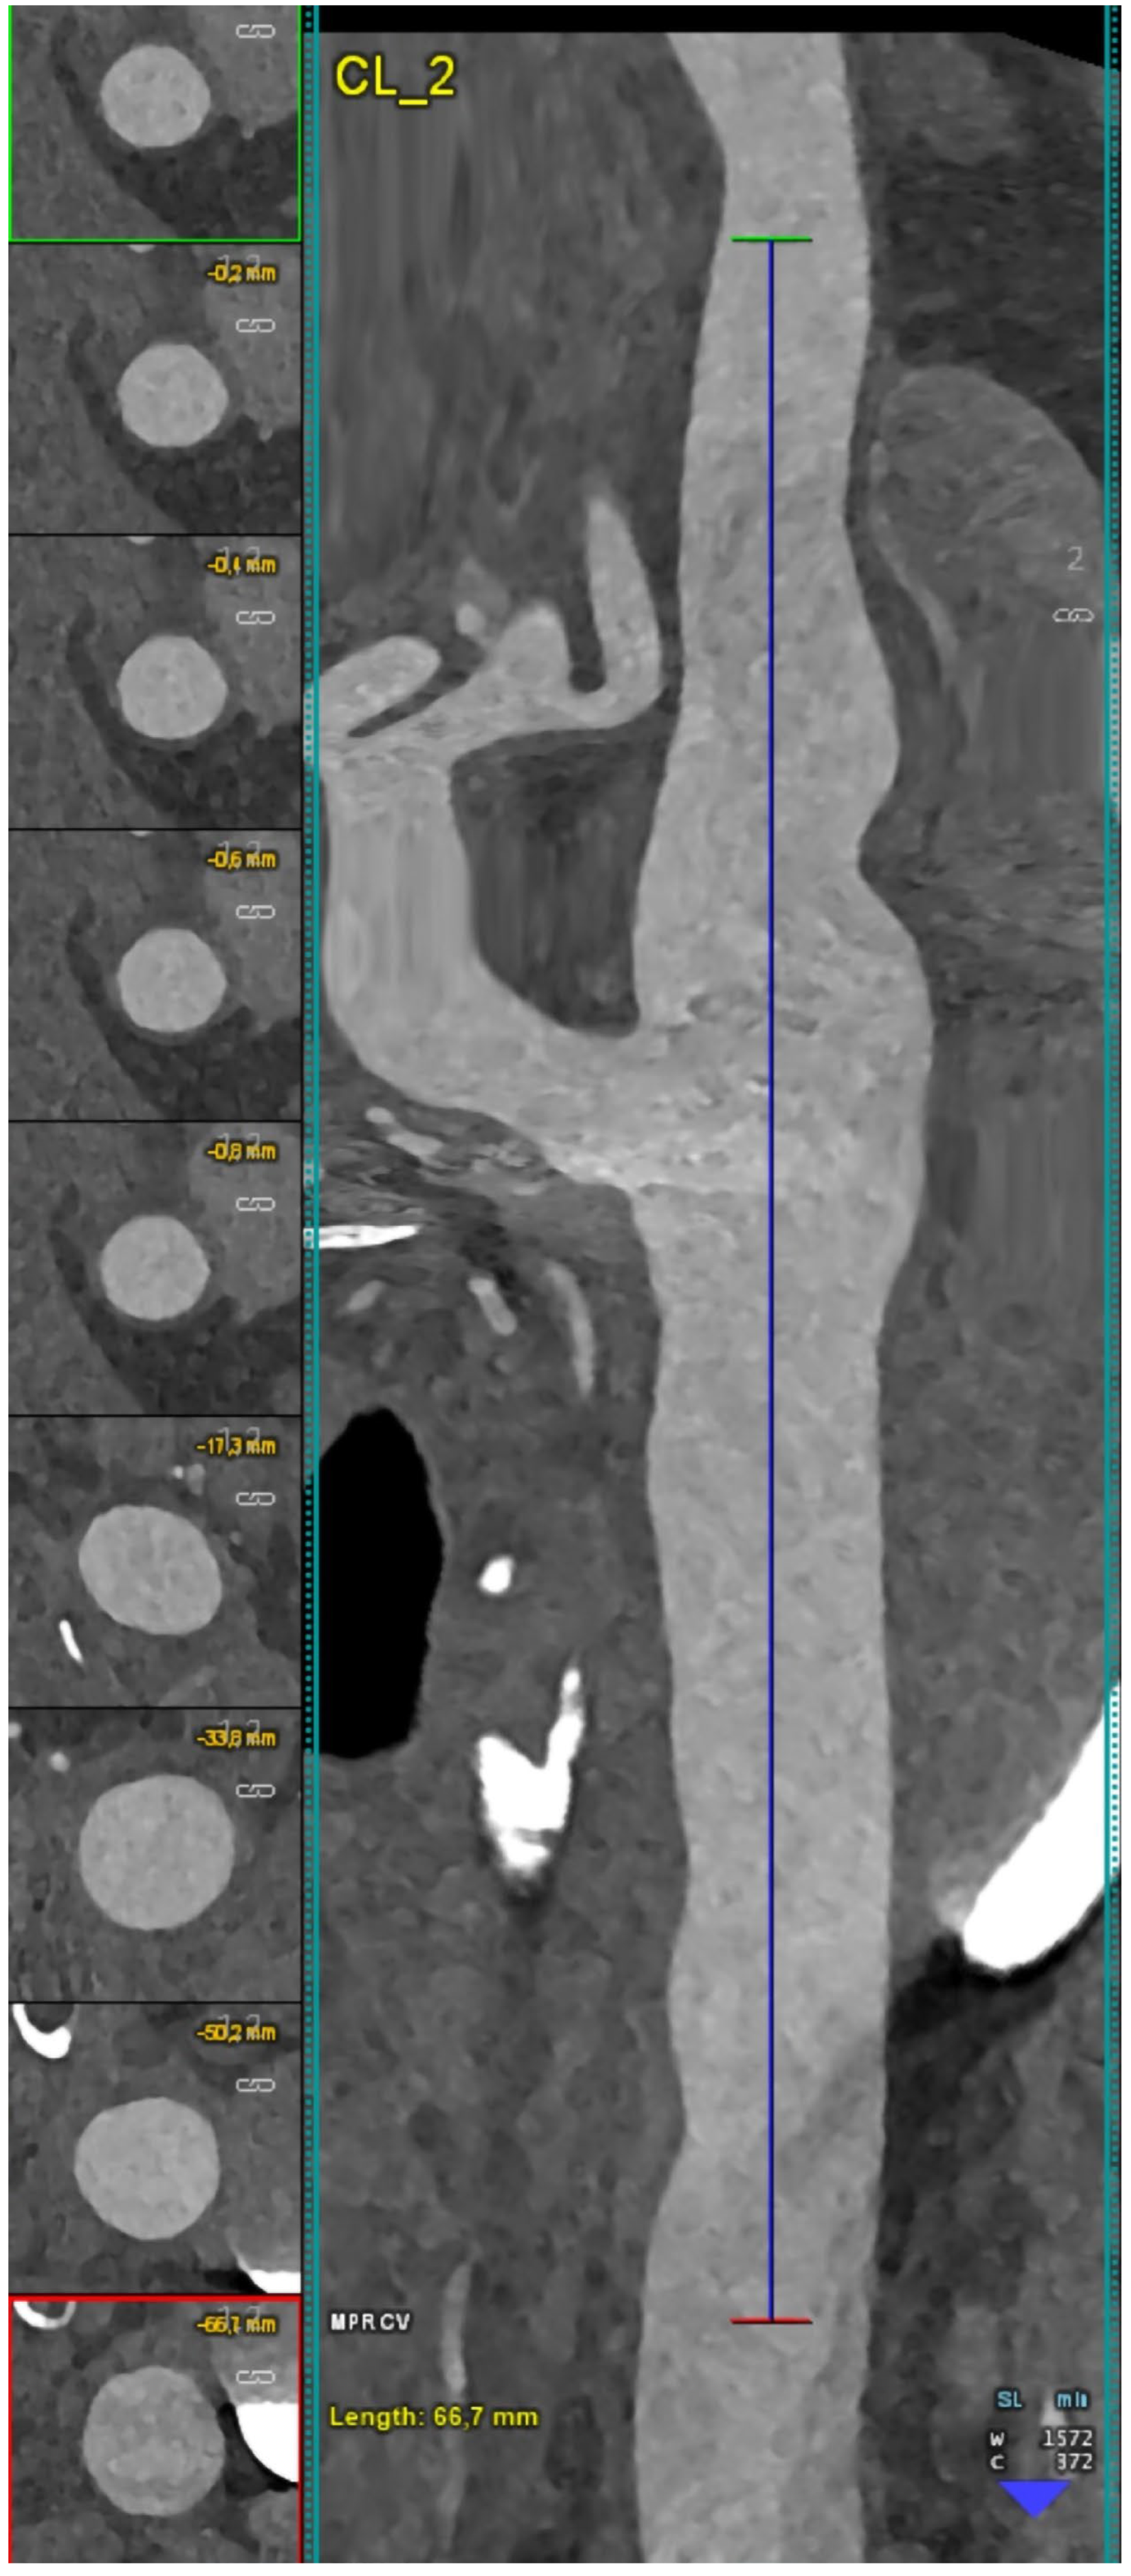

6.5. Calcium Decomposition Algorithms

- Dahal, S.; Raja, A.Y.; Searle, E.; Colgan, F.E.; Crighton, J.S.; Roake, J.; Saba, L.; Gieseg, S.; Butler, A.P.H. Components of carotid atherosclerotic plaque in spectral photon-counting CT with histopathologic comparison. Eur. Radiol. 2023, 33, 1612–1619. [Google Scholar] [CrossRef] [PubMed]

| Dahal et al. [33] | 2023 | Ex vivo (human) | 20 | Tissue analysis | FC thickness and FC area did not show significant differences between the SPCCT-derived radiological measurements and the histopathological measurements (p-value range 0.15–0.51 for FC thickness and 0.053–0.30 for FC area). |